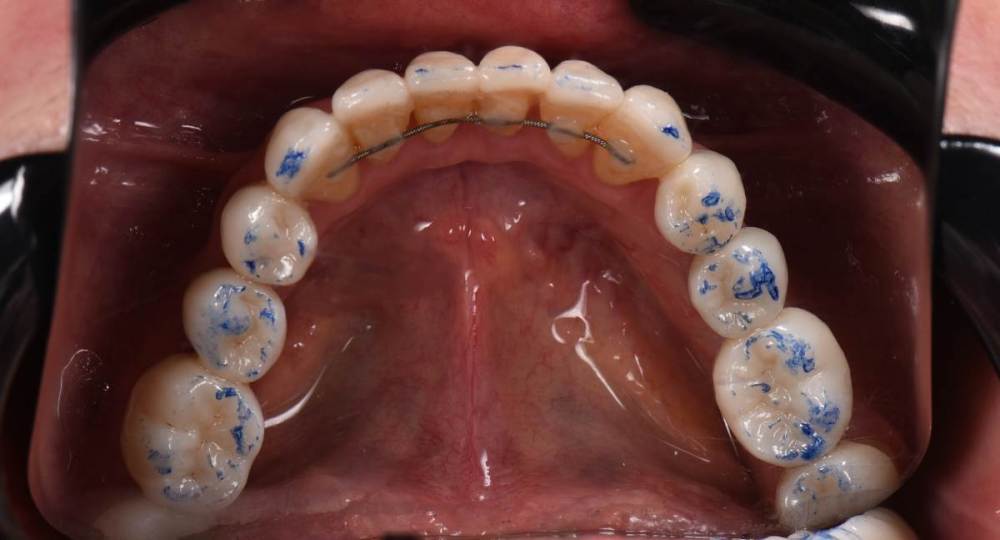

Брукс чекеры:

DSC_0402.thumb.JPG.9053cba49785bf22984aecb4de6cbc02.JPGDSC_0403.thumb.JPG.2015cfab9c333c8bf57e8b673ced91ac.JPG

Закончил тотал и решил поделиться. Протезировали с учетом положения ВНЧС в концепции Славичека.  В конце изготовление брукс чекеров для проверки нежелательных контактов во время сна.  Гигиену пытаемся победить...